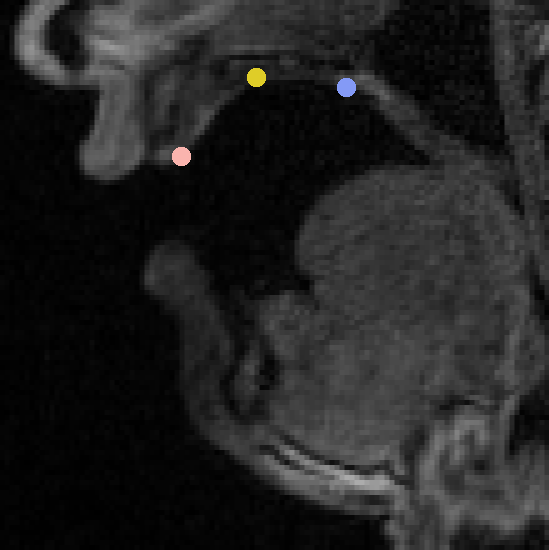

First, we have to find the optimal scale and location in the point cloud for the mesh generated by the mean of our model. This step is necessary because our shape space is not able to produce rigid transformations like translations or rotations. We use the following approach to facilitate this process: on the mesh, we selected 7 vertices as landmarks, as shown in Figure 1. Here, we see that we used three landmarks along the mid-sagittal line of the palate: one at the incisors, one at the hard/soft palate boundary, and another at the point of greatest curvature. In order to add lateral information, we used the latter two landmarks as the anchor for two additional landmarks at either side of the palate.

Afterwards, we find the points in the data corresponding to these landmarks. If the used cloud originates from an MRI scan, this scan can be used to derive the coordinates like in Figure 2. Here, it is evident that the landmark locations are relatively easy to identify for a user. The scale and position of the mesh are then determined by finding the best rigid transformation that maps the user-provided coordinates to the landmarks on the mesh. Additionally, an iterative closest point (ICP) approach [4] was applied to further improve this rigid alignment.